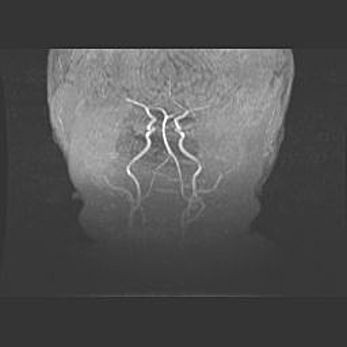

Лейкомаляция с кистозно-глиозной дегенерацией головного мозга.

Возраст: 2 месяца 25 дней

Вес: 6400 г

Окружность головы: 40 см

Срок гестации: 41 неделя

Лейкомаляцию относят к ишемически-гипоксическим повреждениям головного мозга, диагностируемым у новорожденных. При лейкомаляции в головном мозге обнаруживают очаги некроза, возникшие после тяжелой гипоксии и нарушения кровотока. В процессе морфогенеза очаги проходят три стадии: 1) развития некроза, 2) резорбции и 3) формирования глиозного рубца или кисты. Перивентрикулярная лейкомаляция (ПЛ) встречается примерно в 12% случаев среди новорожденных, обычно – у недоношенных детей, причем, частота ее зависит от массы, с которой младенец появился на свет. Наибольшее число малышей страдает лейкомаляцией, если масса при рождении 1500-2500 г.